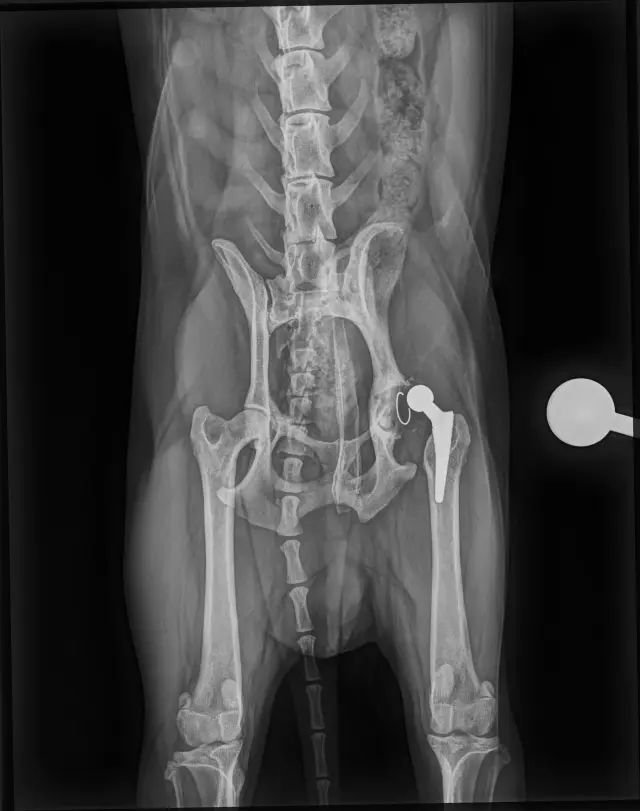

Sbírka je pro aktivního pejska Charlieho (Káju), který v říjnu 2025 podstoupil operaci cementované endoprotézy levé kyčle kvůli degenerativní coxartzróze. Samotná operace bez předoperačních a pooperačních kontrol vyšla na 64tis. Po dlouhé rekonvalescenci se opět vracel k normálnímu životu. Začalo se opět chodit na procházky, zatím ne žádné túry a vypadalo to, že vše bude v pořádku. Kontroly dopadli dobře, Charlie chodil i radostně pobíhal bez potíží. Už jsme si mysleli, že konečně bude mít klid od bolesti, ale bohužel začal náhle kulhat a chodit zadní částí těla do pravého boku. ❤️‍🩹

Nechali jsme tedy na veterině udělat orientační RTG snímky, bez přítomnosti ortopeda, byla již vidět luxace implantátu, proto jsme i během víkendu zkontaktovali MVDr. Jana Hnízda, který ho operoval a hned nás následující den pozval na RTG v sedaci. Bylo tedy zjištěno, že cement, který pojí umělou jamku s kostí se uvolnil a celý implantát jde tak v určitém pohybu do subluxace. 😥

Dorazili nám dnešní snímky, už ortopedicky přesnější